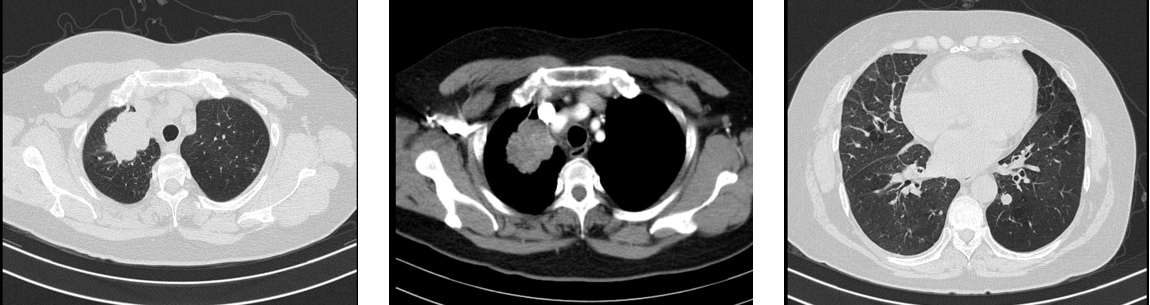

胸部CT(2020-08-05):右上肺尖段巨大肿块,伴两肺多发结节。

病理诊断(2020-08-05):肺腺癌。

基因检测:EGFR 19del突变。

临床诊断

肺腺癌伴双肺转移(cT2N2M1,IV期)。

一线治疗(2020-08至2022-02)

方案:奥希替尼80mg QD

疗效评价:PR

PFS:18个月

胸部CT(2022-02):右上肺病灶较前增大,肺内转移灶进展。